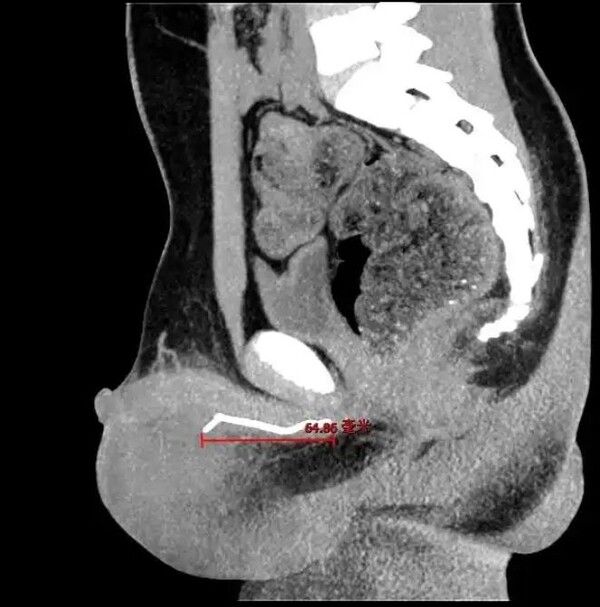

의료진은 종양 가능성을 의심해 CT 검사를 시행했고, 그 결과 소년의 요도 깊숙한 곳에서 길이 약 7cm의 철사를 발견했다.

이는 마스크 코 지지대인 것으로 밝혀졌다. 요도에서 삽입돼 음낭 부위까지 도달해 있었다.